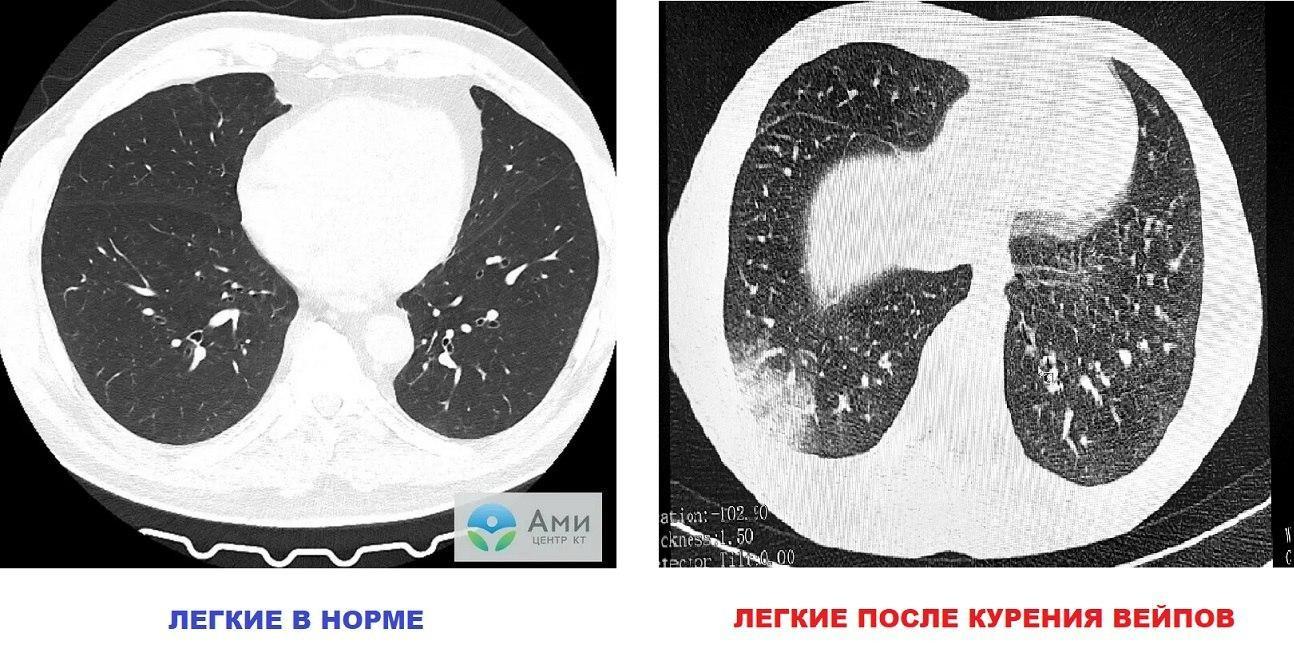

То же самое происходит со всеми остальными заболевшими — большинству диагностируют тяжелые поражения легких — EVALI и облитерирующий бронхиолит. По сравнению с прошлым годом, таких обращений стало на 30% больше.

Врачи по всему миру уже давно бьют тревогу — все больше и больше людей страдает от инфекции EVALI. Аббревиатура EVALI — E-cigarette and Vaping use-Associated Lung Injury — с английского переводится как «повреждение легких, ассоциированное с курением электронных сигарет».

EVALI — это острое легочное повреждение, спровоцированное курением электронных сигарет. О болезни впервые заговорили в 2019 году — тогда в США было зарегистрировано 3000 случаев этой инфекции. Однако, должное внимание ей оказать не смогли — в 2020 году началась пандемия коронавируса. Симптомы заболеваний из-за влияния на дыхательные пути схожи, поэтому различить их было практически невозможно.

фото: Shutterstock/Fotodom.ruУ людей, курящих сигареты, болезни, поражающие дыхательную систему, развиваются спустя долгие годы — среднем необходимо около 10 лет. EVALI же все чаще встречаются у людей с меньшим стажем курения, преимущественно — очень молодых. К сожалению, в России среди курящих вейп довольно много подростков и меньше их не становится, несмотря на недавно вступивший запрет на продажу вейпов несовершеннолетним.